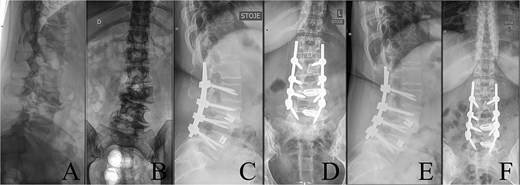

Last preoperative X-ray, lateral (A) and anteroposterior view (B). After 10 weeks of follow-up; lateral (C) and anteroposterior view (D). After 1 year of follow-up; lateral (E) and anteroposterior view (F).

Postoperatively, the patient experienced left psoas and quadriceps femoris muscle paresis, with the latter gradually improved to near-normal before discharge. No other complications were observed. At the 10-week follow-up, the left quadriceps had regained full strength, but partial paresis (3 out of 5) of the psoas muscle persisted, resulting in gait disturbance. At the final follow-up, one year after surgery, imaging showed L2-L4 fusion with no signs of instability or residual deformity (Fig. 4). The patient’s back pain resolved. A normal muscle function was observed.